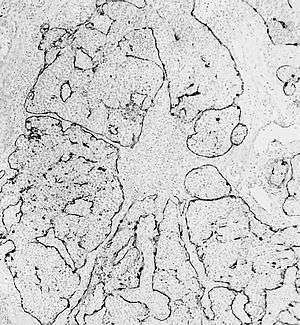

Esthesioneuroblastoma is an extremely rare form of cancer involving the nasal cavity. It can cause loss of vision and taste.[1][2][3] It is often considered synonymous with "olfactory neuroblastoma"[4] and is believed to arise from the olfactory epithelium, but the exact tissue of origin is not yet well characterized. It is associated with trisomy 8.[5]